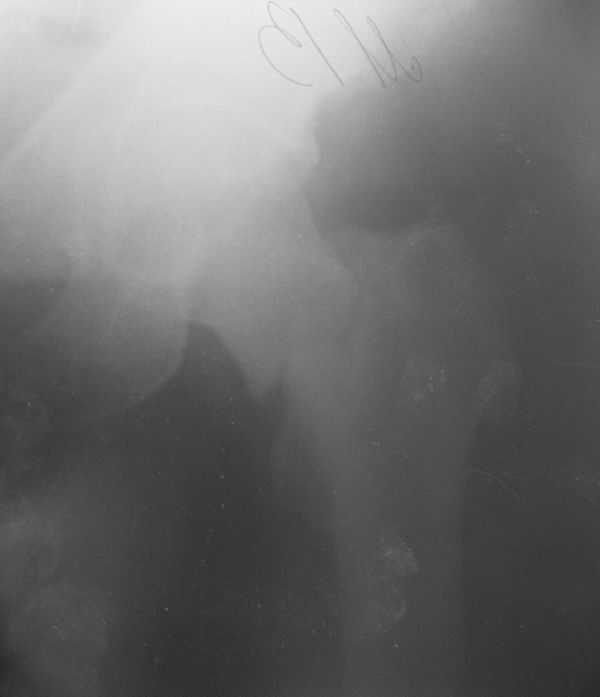

Уважаемые коллеги! Поступил пациент 46 лет после автоаварии от 3.01.

Лечился в ЦРБ. К нам поступил вчера. Имеется оскольчатый перелом диафиза левого бедра, перелом медиального мыщелка, краевой перелом надколенника. У нас, кроме того, выявили перелом шейки бедра. Перелом закрытый, имеется рана в в/3 голени(ниже уровня бугристости б/берцовой кости)без признаков инфицирования.Планируем закрыто фиксировать мыщелок и надколенник винтами, затем закрыто заштифтовать бедро. Вопрос возник по перелому шейки: что предпочесть - длинный PFN или DFN + DHS на шейку?Буду благодарен за ценные советы.С уважением, Станислав Дмитриев.

Заранее приношу извинения за качество снимков. То что есть - либо из ЦРБ, либо сделано в приемном покое, где дежурят рентгенлаборанты различной квалификации. Завтра постараемся сделать снимки всего бедра на длинные кассеты в 2 проекциях. Сейчас больной на скелетном вытяжении. Состояние стабильное.